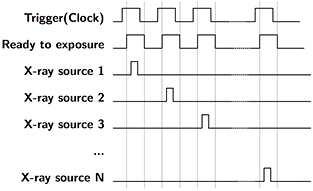

The bench-top chest tomosynthesis system, as shown in figure 1, consists of the CNT linear x-ray source array, a CsI based flat panel detector (Model DRX-1C) manufactured by Carestream Health Inc. (Rochester, NY) mounted on a translation stage, a phantom stage, and an electronic control unit. The detector, which was originally designed for radiographic imaging purpose, has a field of view of 35 × 43 cm and a 139 μm pixel size. The integration time can be adjusted from 260 to 1100 ms. The detector requires a frame by frame external trigger to acquire a sequence of images. Since the x-ray source array used in this study has a relatively short length, the detector and the phantom are mounted on a translation stage to achieve a wider range of imaging geometries. A LabVIEW program was made to automate the x-ray tube operation and image acquisition. As illustrated in the timing diagram in figure 2, the computer generates a sequence of trigger signals to trigger the detector read-out, followed by the detector ready-to-exposure signal which is synced to the x-ray source switching system. The x-ray source switching system is programed to switch and fire each x-ray source based on the sequence set by the operator. The x-ray sources can be fired in any sequence, either one-by-one from one end to the other, or in a pre-defined pattern.

Figure 2. Timing diagram for s-DCT imaging. Computer generates a trigger signal to externally trigger the detector. The detector ready-to-exposure signal is synced to the x-ray source switching system, where each pulse will be used to trigger a single CNT x-ray source in the source array. The CNT sources are fired in a sequence preset by the operator.